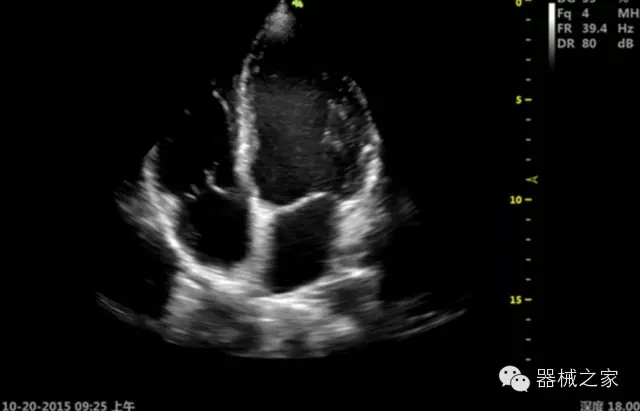

·ICU/CCU;

·飛依諾特有心臟純凈波探頭提供更好的穿透力和彩色敏感度,以及結(jié)合TView梯形拓展改善困難病人深部組織成像;

·獨(dú)有RF敏感血流使得心臟血流完美呈現(xiàn);